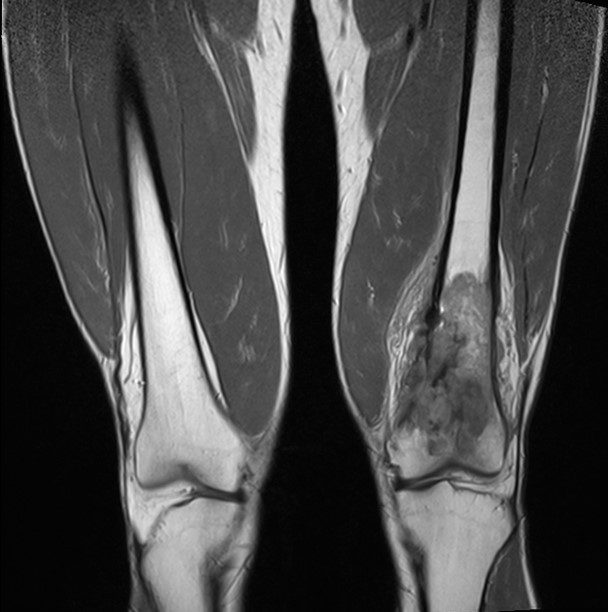

2. Остеосаркома большеберцовой кости

17-летний юноша обратился в МЦ ''Наири'' с жалобами на боли в области коленного сустава. После прохождения обследования у пациента была диагностирована остеосаркома большеберцовой кости.

До операции